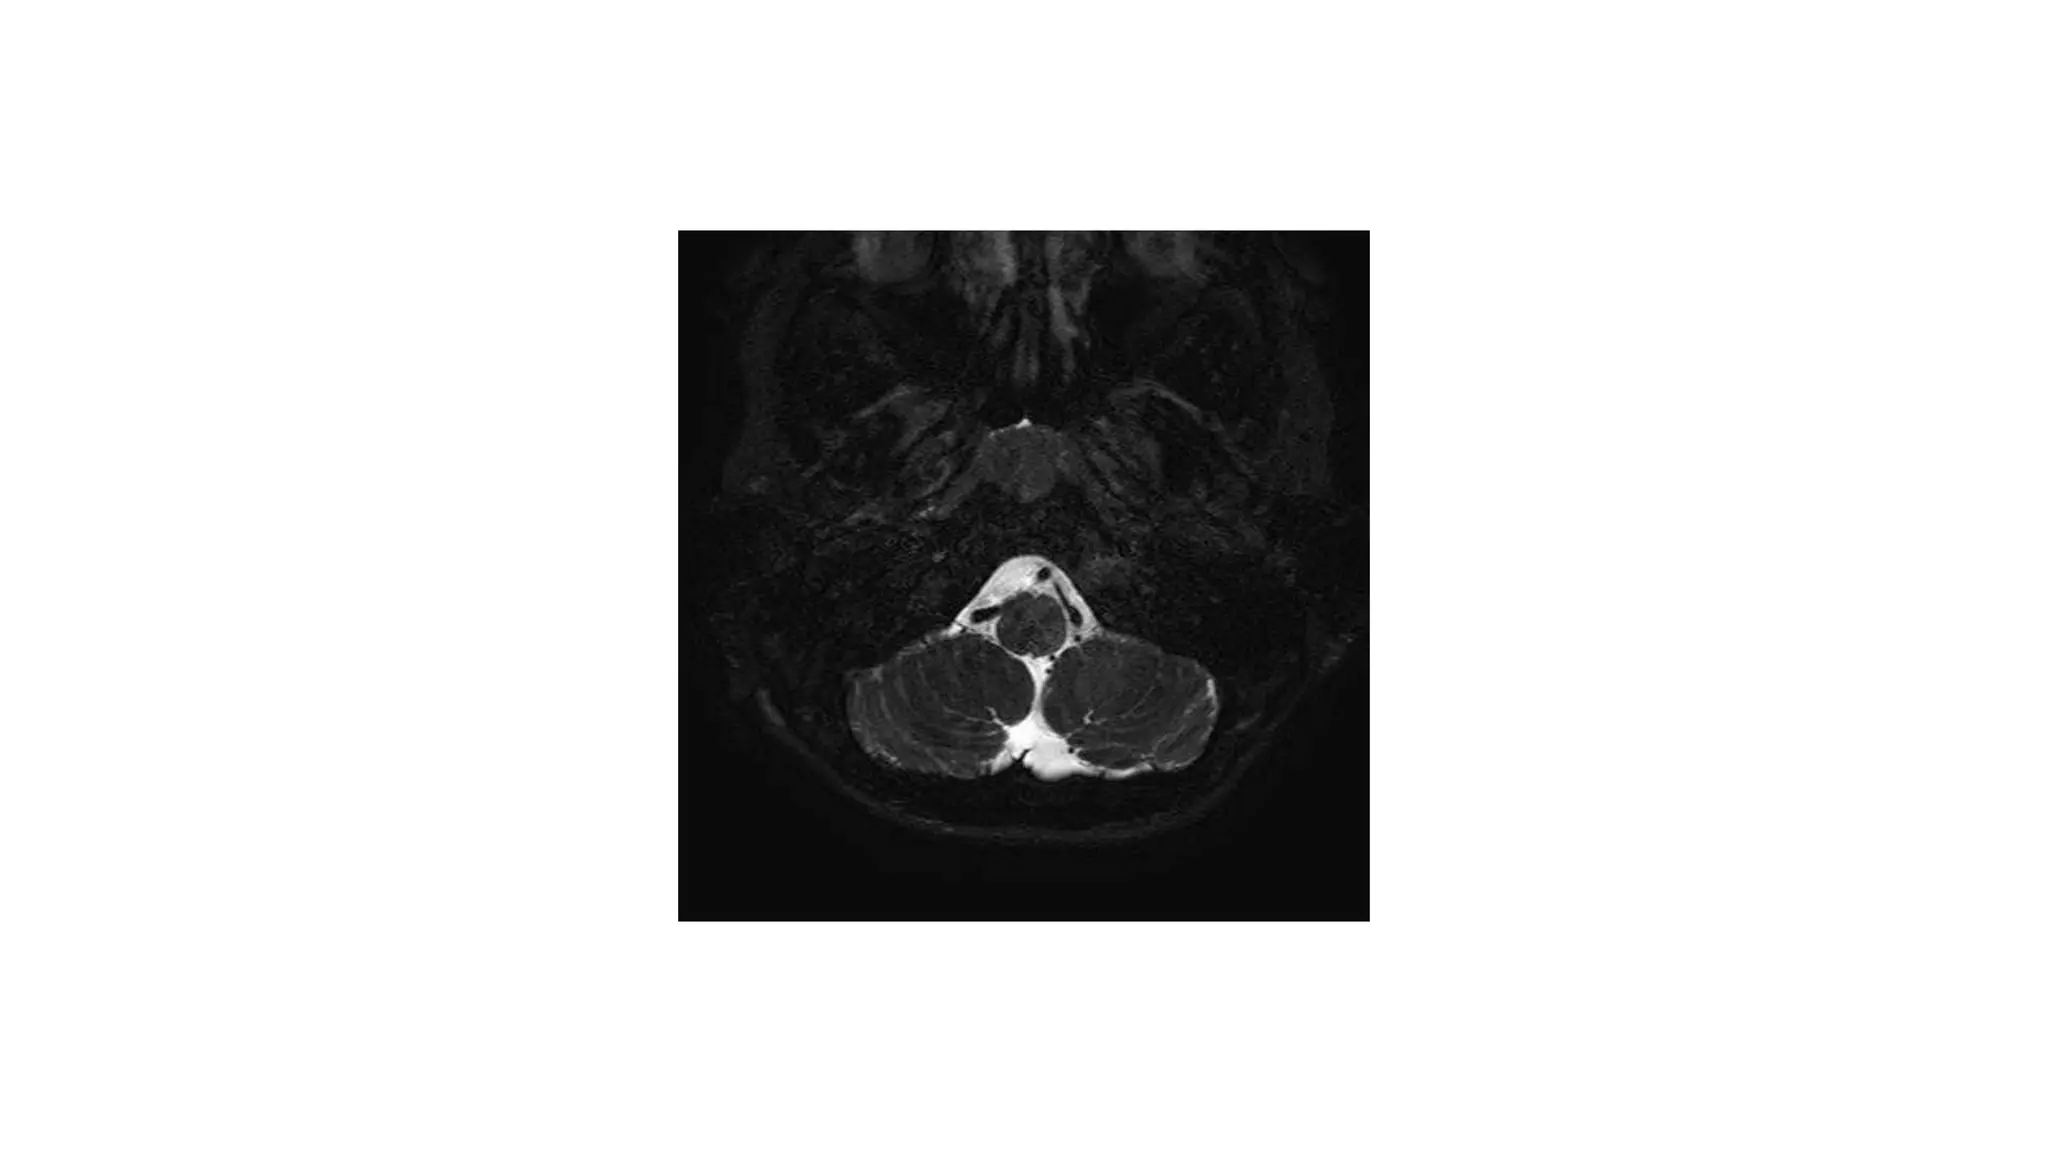

• Epidermoid cyst show restricted diffusion on DWI

Intra-axial tumors